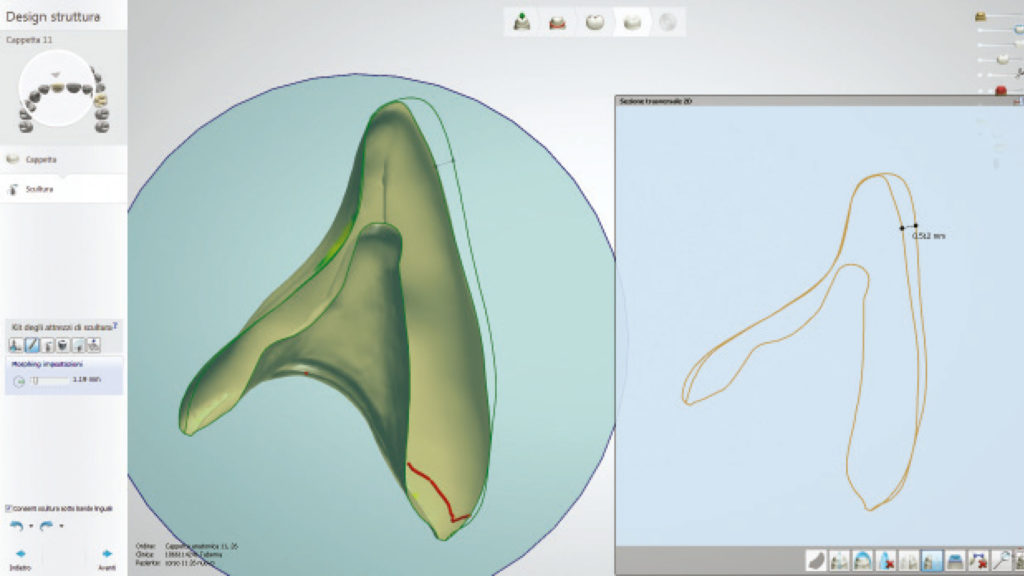

Für diesen Fall ist es von grundlegender Bedeutung, die vom Zahnarzt generierten Pfeiler, so exakt wie möglich zu replizieren, weshalb wir uns für den digitalen Weg entschieden haben (Abb. 27a und b).

In der Software können wir uns im Schnittbild die verfügbare Dicke der zukünftigen Kronen anzeigen lassen, woraus sich wichtige Schlüsse über die mechanische Festigkeit der Versorgung ableiten lassen (Abb. 28). Die Farbanalyse hat zudem ergeben, dass keine komplizierten internen Charakteristika reproduziert werden müssen, und ein ästhetisches Ergebnis leicht zu erreichen ist.